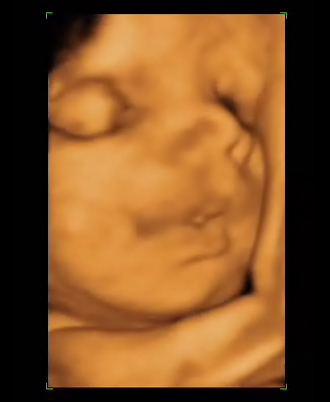

La piel se vuelve tersa y suave gracias al aumento en los depósitos de grasa subcutáneos. Los niños que nacen más tarde suelen tener además un aspecto más arrugado y las uñas largas, de modo que no es inusual observar que se han hecho algún rasguño en la cara.